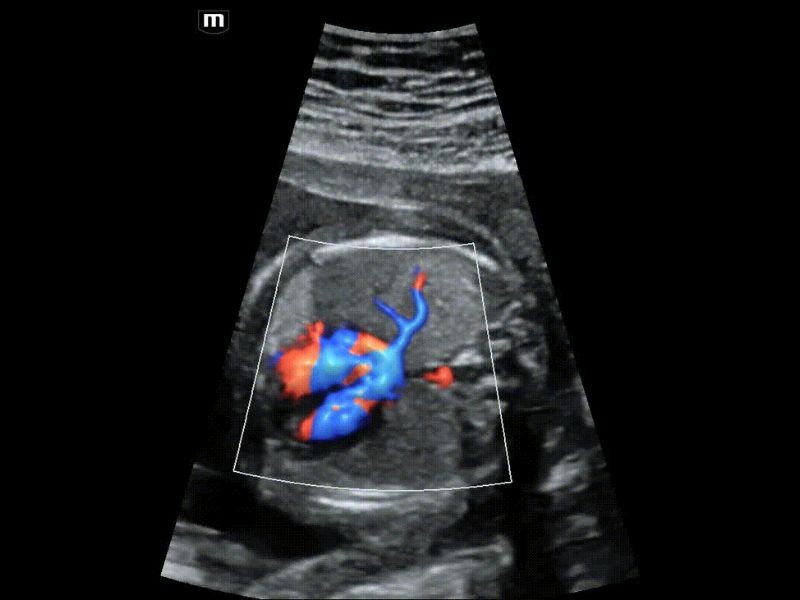

Análise de receptividade endometrial inteligente - Smart-V Trace

O Smart-V Trace detecta efetivamente estruturas anatômicas mesmo com limites fracos, como o endométrio. Além disso, ele fornece uma avaliação abrangente da pegada vascular e a intensidade do fluxo sanguíneo na área alvo é fornecida para apresentar mais informações diagnósticas para receptividade endometrial e distribuição do fluxo sanguíneo do tumor.